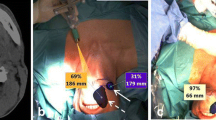

SPECT/CT labelling based on anatomical landmarks (Fig. 3).

Importance of SPECT/CT and low-dose (ld) CT in characterising sentinel lymph nodes (SLN) in the vicinity of primary tumours in oral cavity. On the left (A) SPECT/CT (top) showing uptake in a SLN in level 1a on the left, which corresponds with an enlarged lymph node (circle) on ldCT (bottom). On middle (B) SPECT/CT (top) shows intense uptake in a SLN in level 1b on the right, whereas on corresponding ldCT (bottom) a slightly elongated lymph node (circle) is seen. Finally, on the right (C) SPECT/CT (top) shows drainage from the injection site (IS) to SLNs respectively corresponding with a lymph node cluster in level Ib and a single node in level II of the left side of the neck (circles) on ldCT (bottom)